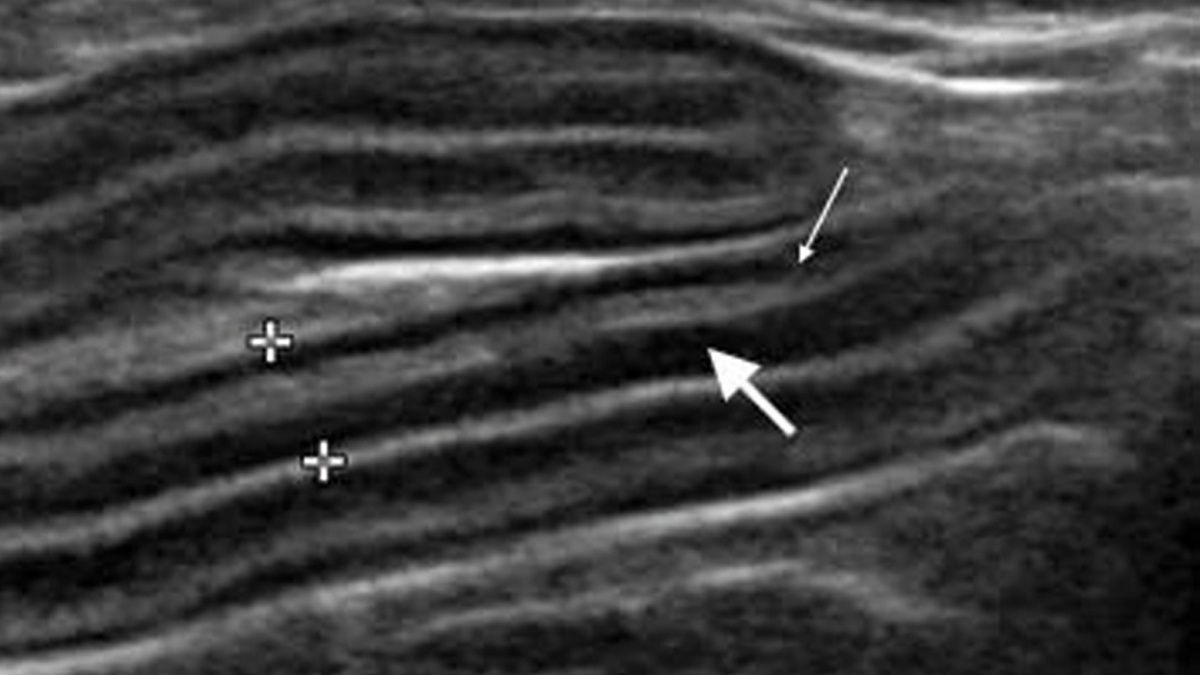

Ультразвукове зображення тонкої кишки в поздовжній проекції у кота з діагнозом ЗЗК. Слизовий шар (товста стрілка) більш виражений, ніж м’язовий шар (тонка стрілка), але це не виключає наявності ДКЛС. Загальна товщина стінки кишківника (між мітками) була збільшена і становила 3,2 мм

Рис. 1. Ультразвукове зображення тонкої кишки в поздовжній проекції у кота з діагнозом ЗЗК. Слизовий шар (товста стрілка) більш виражений, ніж м’язовий шар (тонка стрілка), але це не виключає наявності ДКЛС. Загальна товщина стінки кишківника (між мітками) була збільшена і становила 3,2 мм© S. Al-Ghazlat C. Eriksson de Rezende